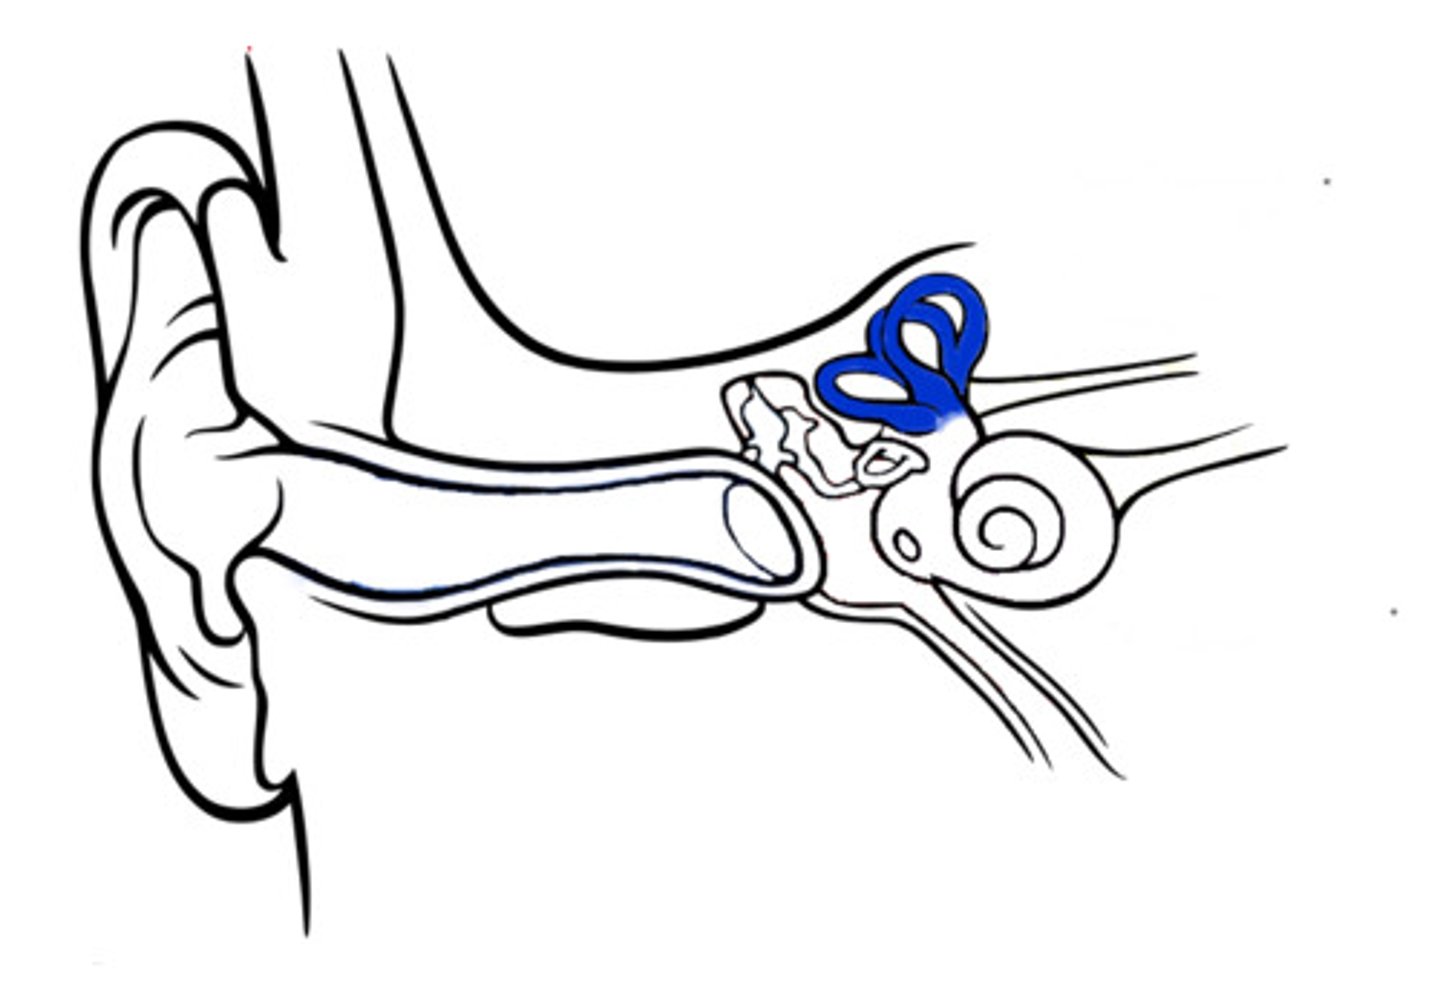

auditory tube

auricle (pinna)

cochlea

cochlear nerve

external auditory canal

incus

labyrinth (osseous + membranous)

(general structure, ignore arrow)

malleus

oval window

round window

scala tympani

section of cochlea

scala vestibuli

section of cochlea

semicircular canals

spiral organ (of corti)

section of cochlea

stapes

temporal bone

tympanic membrane

vestibular nerve

vestibule

vestibulocochlear nerve